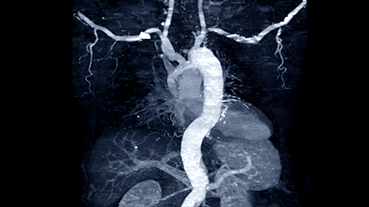

The patient’s severe thrombosis required months of multidisciplinary care and the transplantation of his liver, stomach, large intestine, small intestine, pancreas, and kidney.